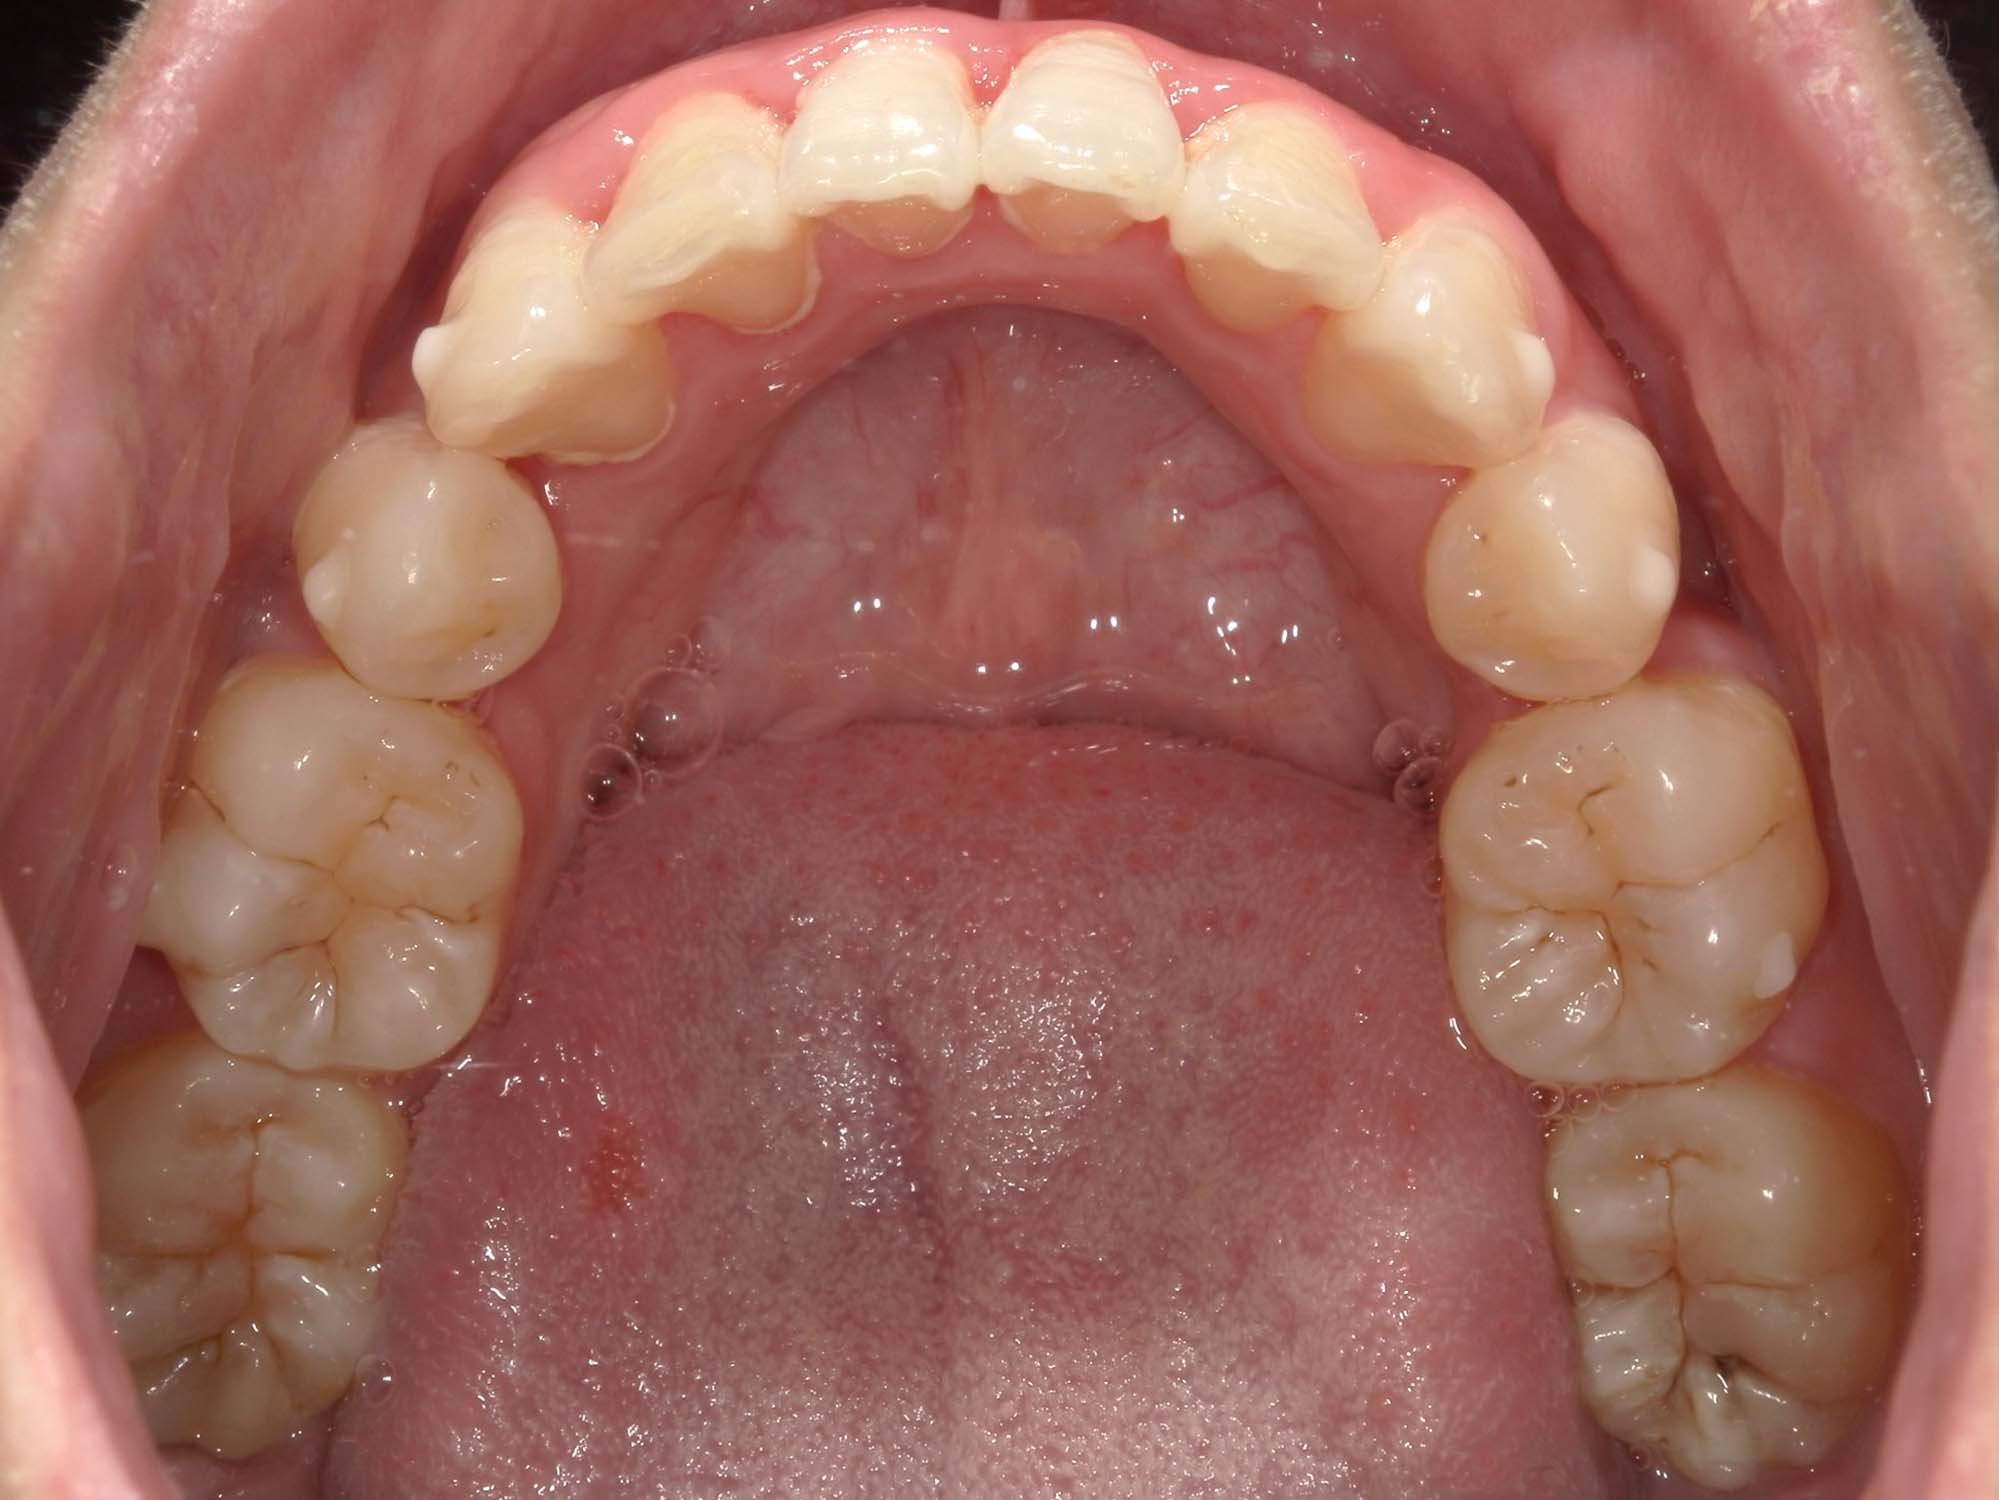

| 年齢・性別 | 21歳 |

|---|---|

| 主訴 | 叢生が気になる・前歯に埋伏歯がある |

| 治療期間・回数 | 6ヶ月 |

| 費用 | 935,000円 |

| 上顎の左側3番が埋伏していたため、上顎左右の3番および親知らずを抜歯し、矯正治療を行いました。 治療開始からおよそ6ヶ月で歯列が整い、審美的にも機能的にも良好な結果が得られた症例です。 |